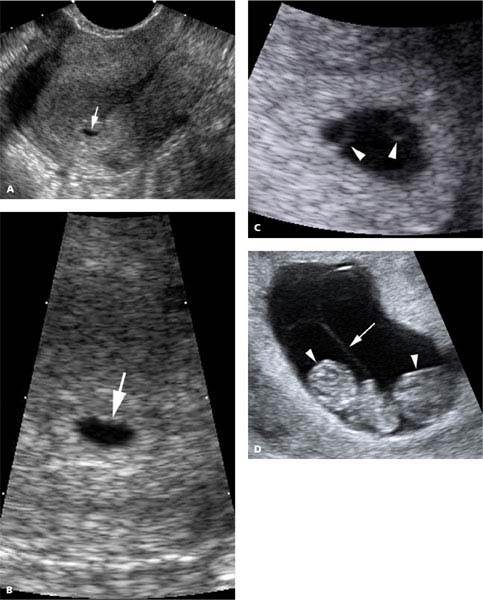

Diagnosis and Characterization of Multiple Gestations | Radiology Key

Conjoined twins in a triplet pregnancy: early prenatal diagnosis with …

Conjoined twins in a triplet pregnancy: early prenatal diagnosis with …